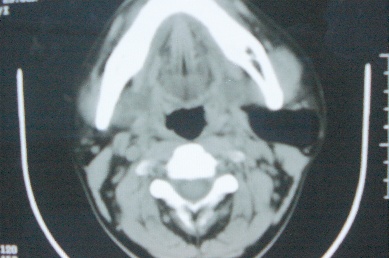

ct10755,男,28岁。发现左侧腮腺区肿块几年,今要求ct检查。左侧腮腺区低密度影,ct值-153hu。

左侧腮腺区囊状低密度影,ct值-153hu,考虑腮腺脂肪瘤。

病灶为一边界清晰脂性区,其内未见实质性组织.支持考虑:左侧腮腺脂肪瘤可能性大.

ct能定性的良性肿瘤不多,对脂肪瘤的诊断是比较有把握的,加大窗宽还可以看到里面有分隔

ct值-153hu,腮腺脂肪瘤。